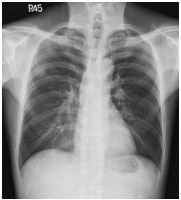

3. This 72-year-old diabetic man was taken to ER for productive cough for 10 days, and rapid progressive dyspnea for 2 days. He also had fever and chill for a week.